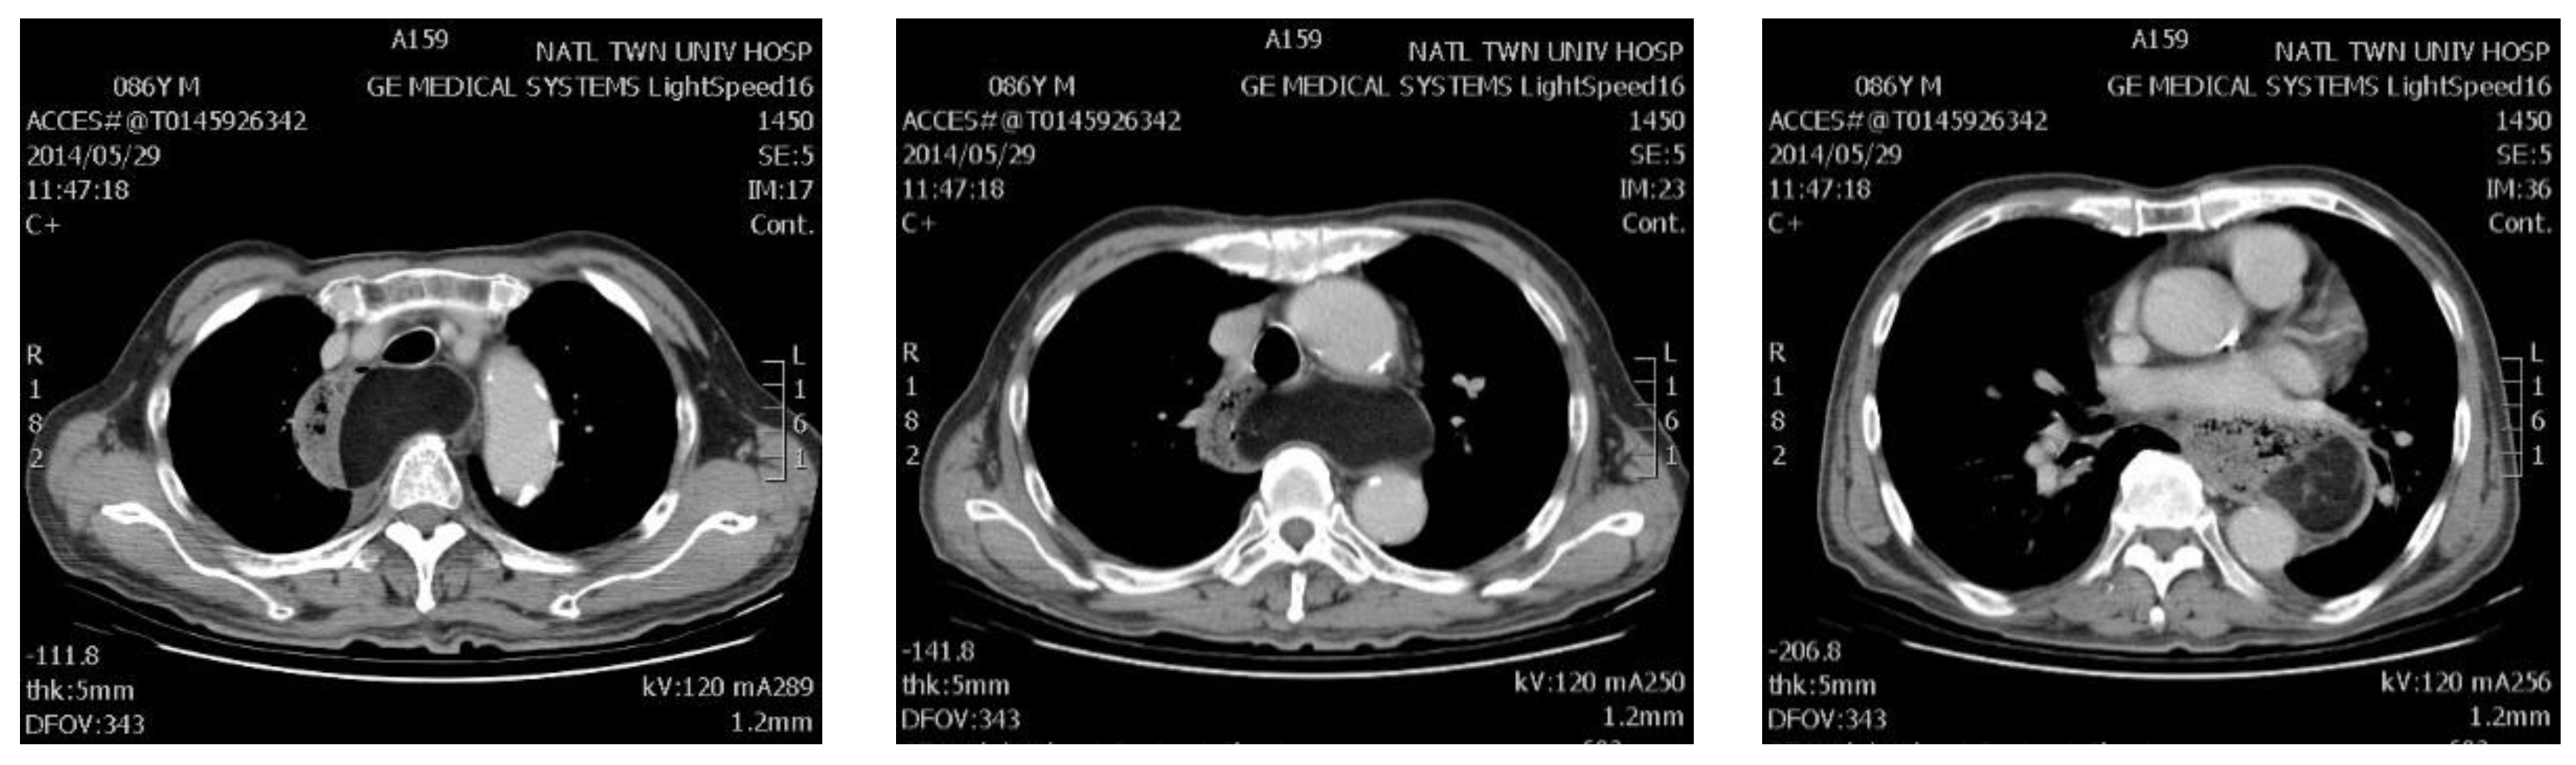

| 16 | 67/M | Lt ★ | 10 | Dysphagia | GIST ◆ | 241 * | 53 |